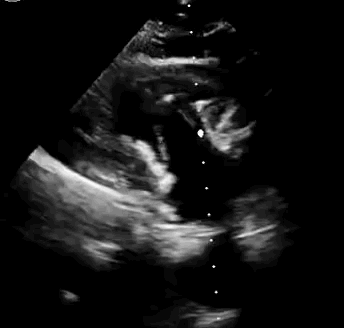

上海中山醫院葛均波院士、錢菊英院長、周達新教授、潘文志教授、潘翠珍教授、李偉教授共同完成此次臨床前研究。 術後葛均波院士對Lux-Valve Plus的器械操作效能給予了高度評價,DSA和超聲影像也顯示出在本次研究中Lux-Valve Plus的安全性和有效性俱佳。

本次臨床前研究經右側頸靜脈置入LuX-Valve Plus輸送系統可調彎鞘管,在DSA及超聲引導下將人工三尖瓣瓣膜植入到原有三尖瓣位置,利用獨特的錨定科技將人工瓣膜支架固定在預定的位置。